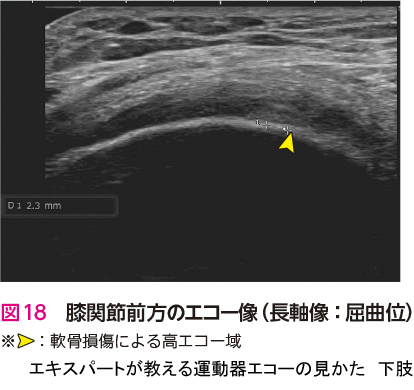

症例 7大腿骨内顆軟骨損傷

前述のように変形性膝関節症においてエコー検査の診断価値は低い.また,私自身も図18のエコー像で初診時に指摘できる自信はない.しかし,エコー検査を用いることで,注射をさまざまなポイントにエコーガイド下に安全かつ正確に打つことができる.そのため,私にとって形性膝関節症の診療におけるエコー検査は変必要不可欠なツールとなっている3).